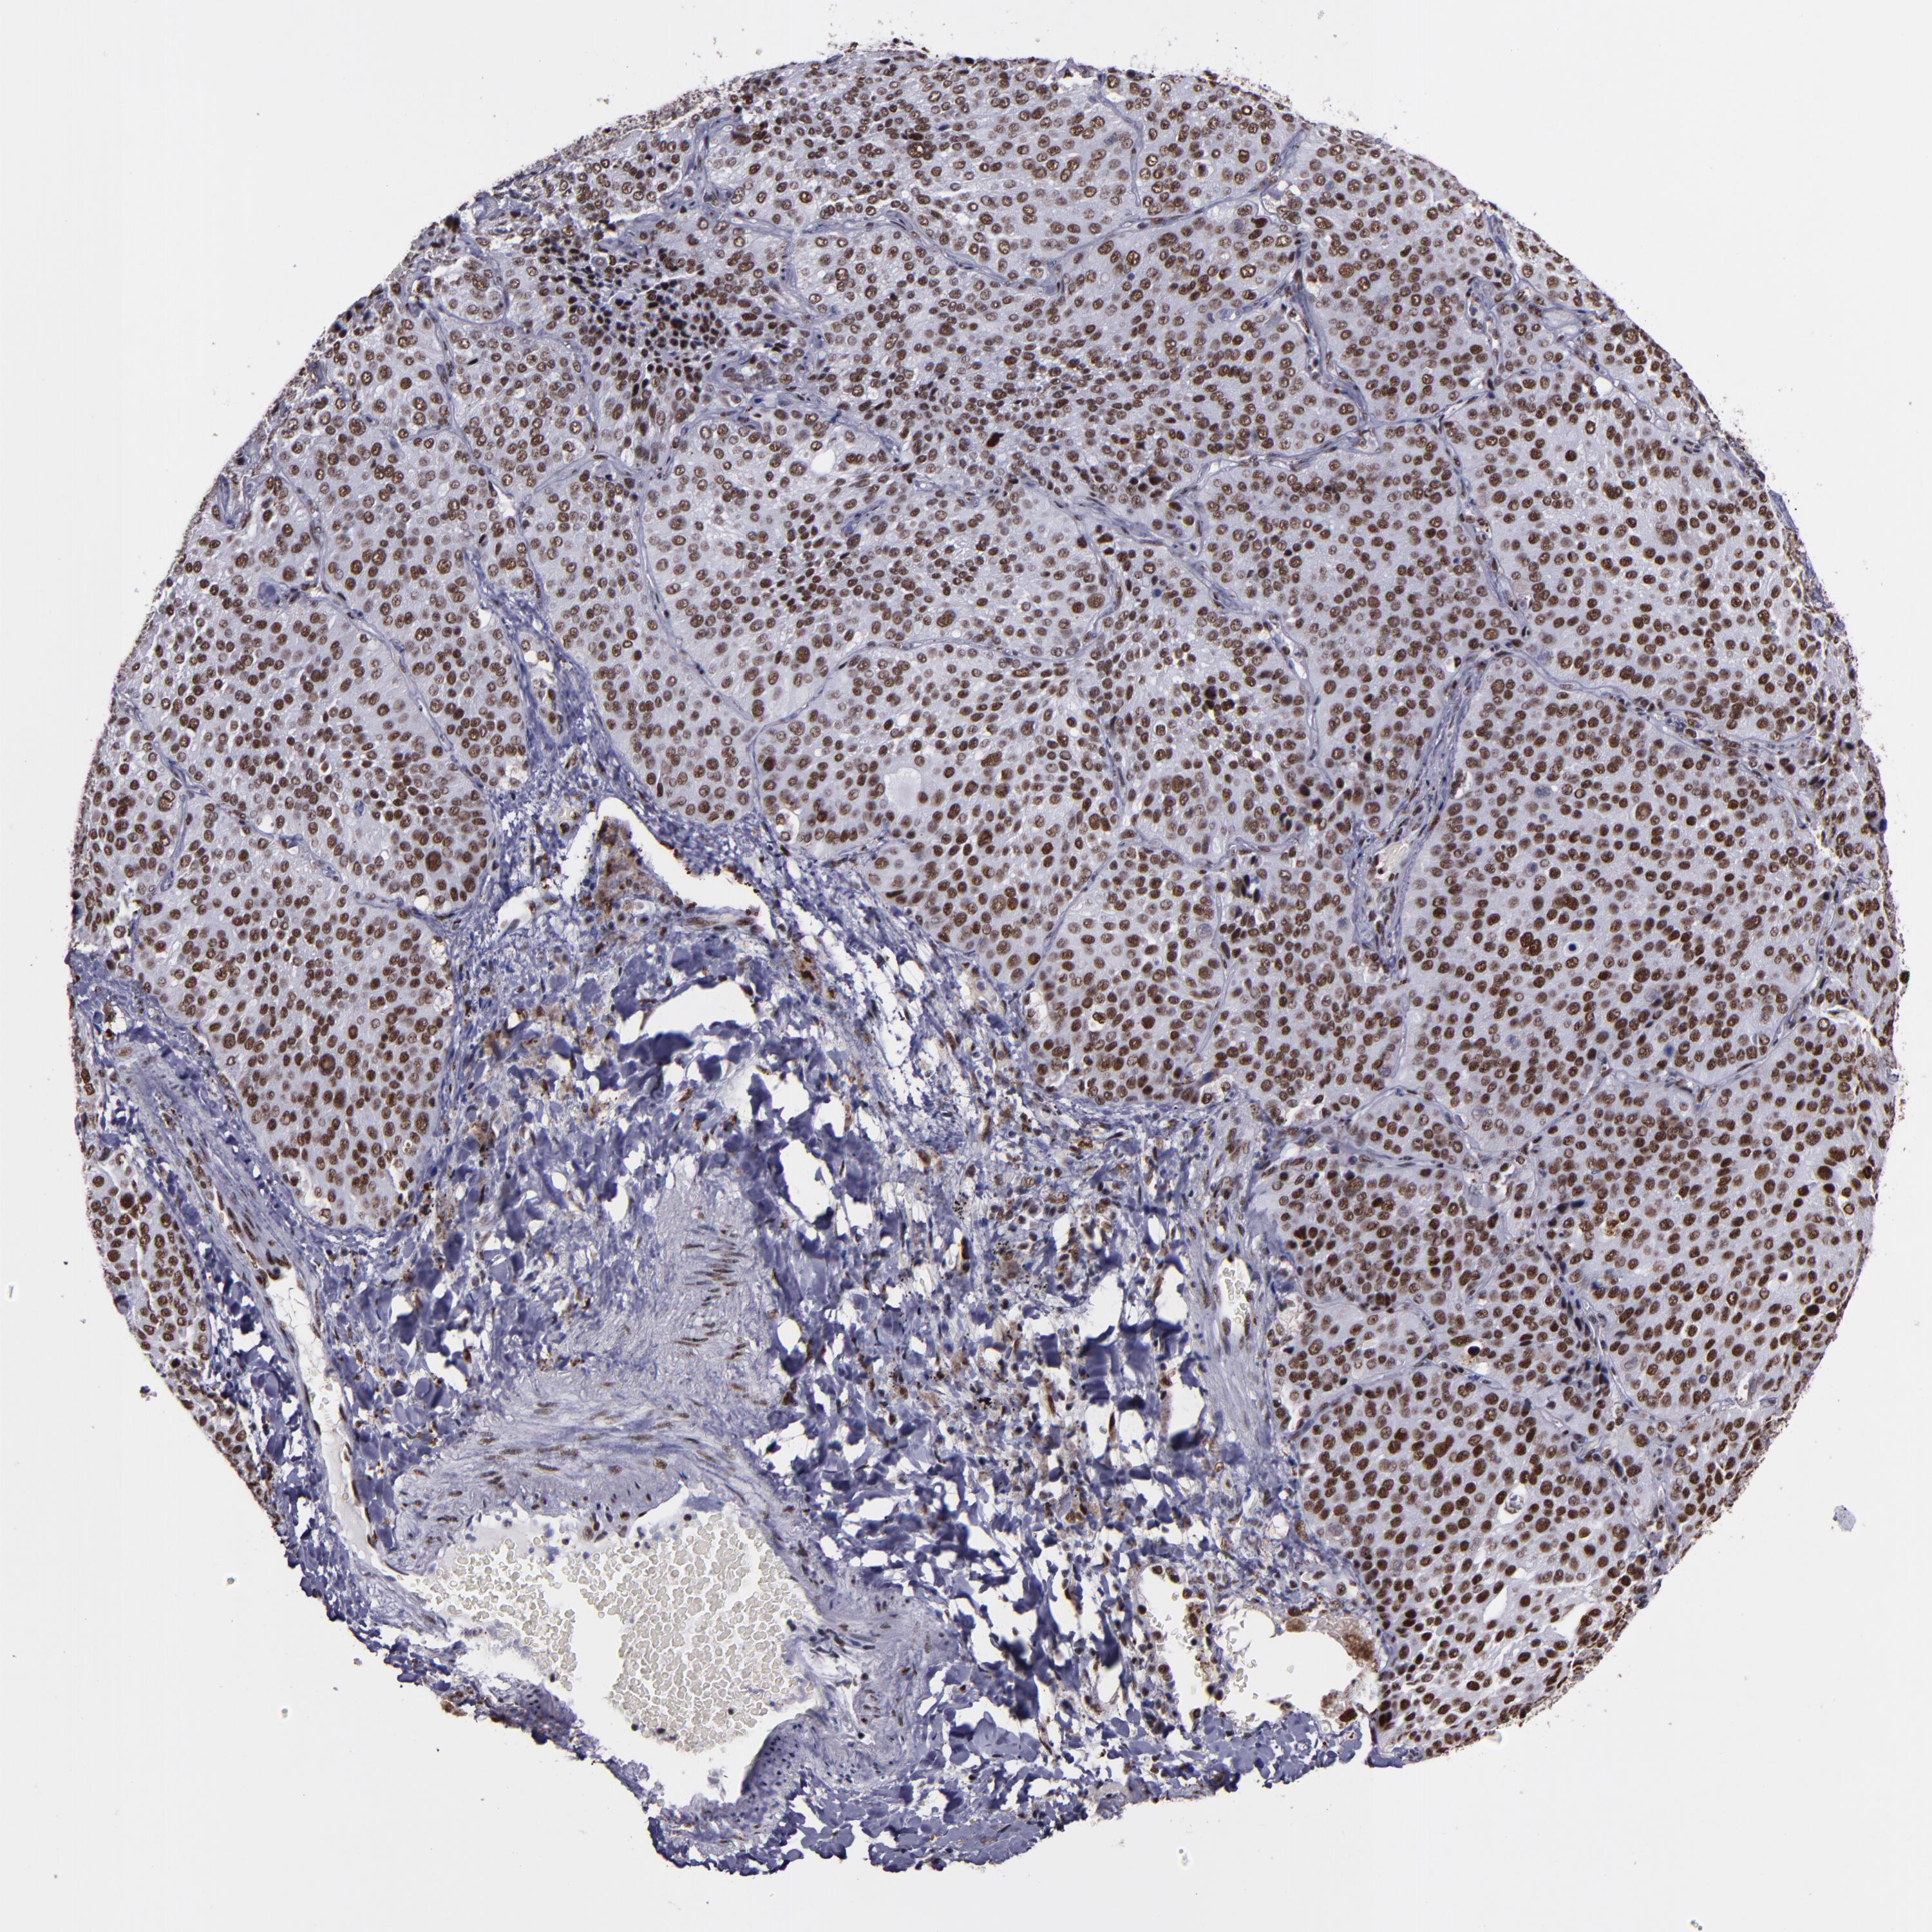

CANCER LUNG CANCER Show tissue menu

LUAD TCGA LUAD VALIDATION LUSC TCGA LUSC VALIDATION PROTEIN LUAD CPTAC PROTEIN LUSC CPTAC PROTEIN EXPRESSION

ANTIBODIES

AND

VALIDATION